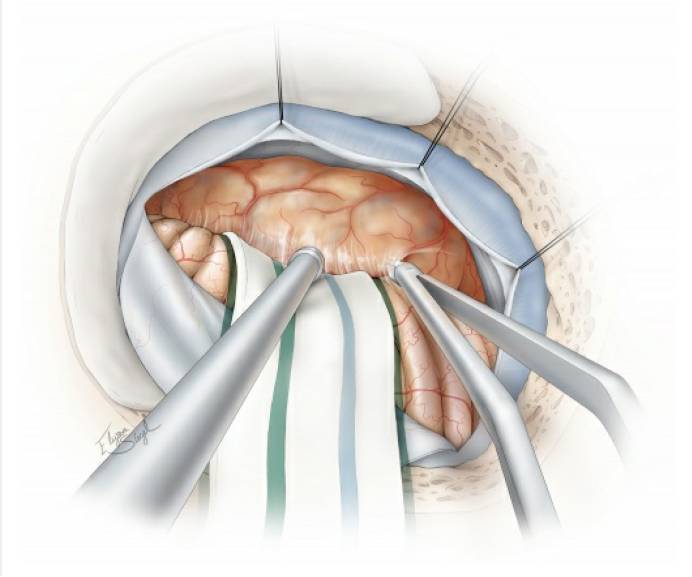

图4. 硬膜下初步暴露位于左侧的肿瘤。注意图中所示:去除乙状窦表面的骨质后,可以用缝线沿乙状窦边缘悬吊,将乙状窦牵开,获得更好的手术视野(扩大乙状窦后入路。译者注)。如果没有预置腰大池引流,则可通过打开后组颅神经周围的脑池释放脑脊液。随后,分离肿瘤后缘与小脑表面的蛛网膜粘连。

图5. 显示颅神经的大致分布与内听道后型肿瘤前缘包膜的关系。术前仔细研究MRI可使术者形成对肿瘤病理解剖以及重要解剖结构部位的立体构象。